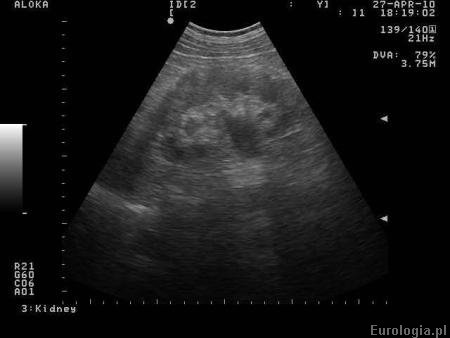

Fot. Obraz nerki z zastojem w UKM.

Poszerzenie UKM - zastój moczu w układzie zbiorczym nerki obserwowany jest w badaniach obrazowych układu moczowego - np. USG, urografii lub tomografii komputerowej. Zastój moczu w UKM świadczy o utrudnionym odpływie moczu z nerki, którego przyczyna zawsze wymaga diagnostyki.

Najczęściej poszerzenie UKM obserwuje się u pacjentów z kamicą moczowodową oraz nowotworami miednicy małej - rak pęcherza, rak gruczołu krokowego oraz nowotwory narządu rodnego u kobiet. U młodych pacjentów często obserwuje się poszerzenie UKM w przebiegu zwężenia połączenia miedniczkowo - moczowodowego. Czasami zastój moczu w układzie zbiorczym obserwowany w badaniu USG nie potwierdza się w urografii a jego przyczyną są torbiele centralne nerki imitujące zastój w UKM